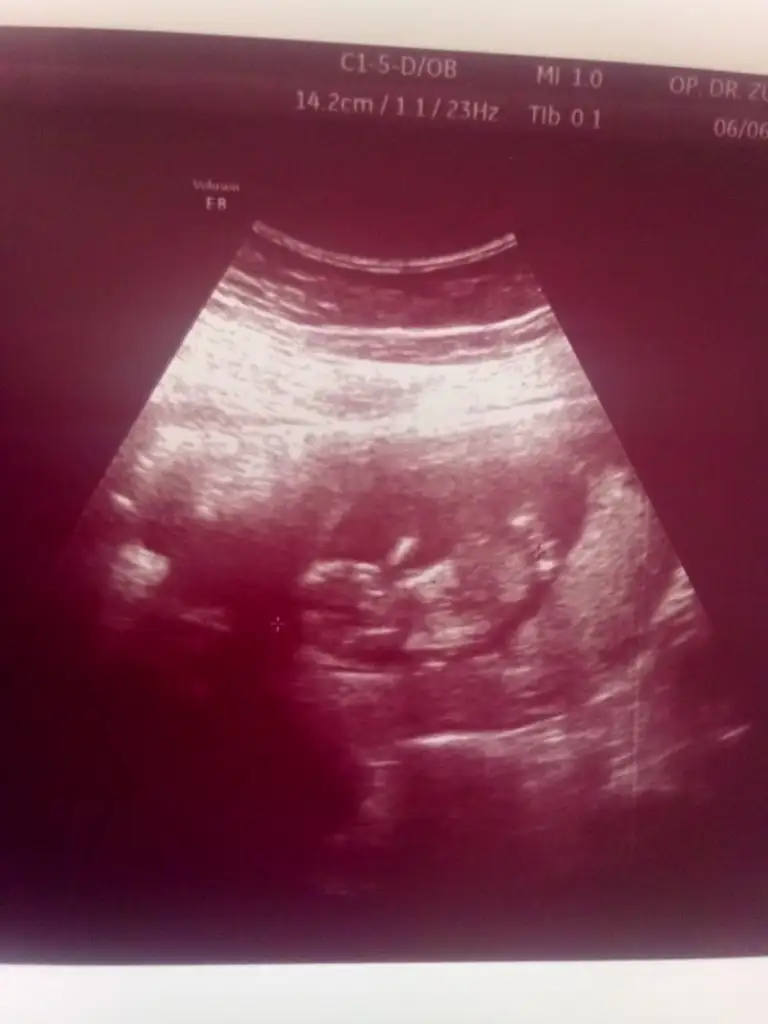

Kızlar benimkine de bi bakabilir misiniz

Eklentiler

• Screenshot_20210609_082926_com.android.gallery3d.webp

Screenshot_20210609_082926_com.android.gallery3d.webp

11,9 KB · Görüntüleme: 84